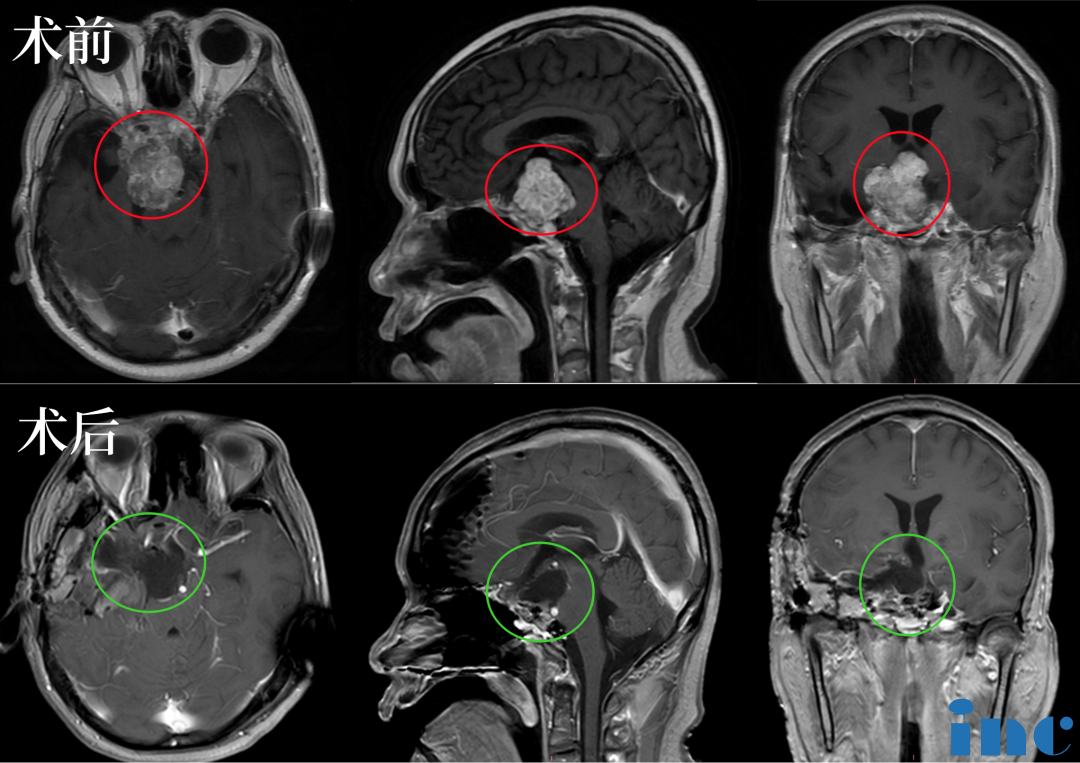

“5月8号咨询法国教授,然后到5月15号就手术了,真的很快、很及时。”苏先生一家选择手术时并没有太多犹豫,他们知道这一次机会来之不易。2023年5月15日,INC法国Froelich教授为苏先生做了四次开颅手术,在术中,Froelich教授联合应用显微镜和内镜,运用的“筷子手法”,术后当晚核磁显示肿瘤已基本全切。这对夫妻是幸运的,在这场风险较大、具挑战的手术中重获新生。

术后:手术顺利,术中将鞍上鞍内、海绵窦区、三脑室肿瘤切除